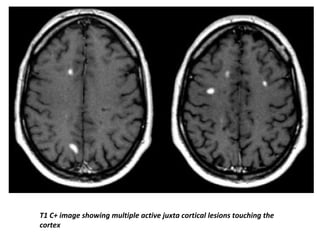

T1 C+ image showing multiple active juxta cortical lesions touching the

cortex

T1 C+ imageshowing multiple active juxta cortical lesions touching the cortex